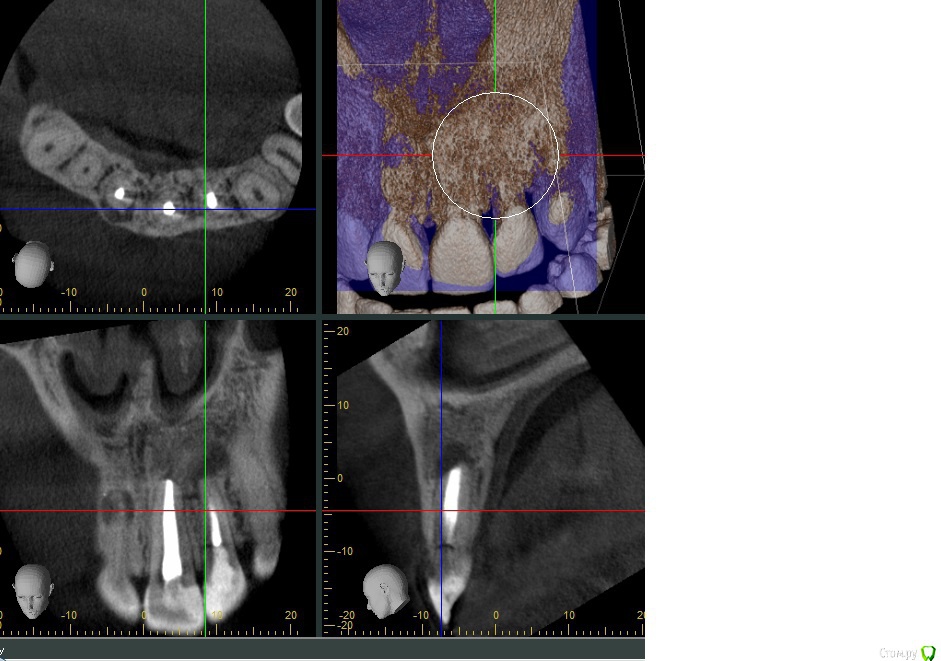

Doctor Vlad Опубликовано 29 августа, 2016 Поделиться Опубликовано 29 августа, 2016 Добрый день, уважаемые доктора!Оцените возможность сохранения 11 зуба с маргинальной и апикальной резорбцией зуба. причину на кт не нашел, но корень тоже поеден. переломов не определил. пломбирован гомогенно! мб перегрузка штифта? зубы 21 и 22 ранее ( 2 года назад по словам) сделана рвк; есть смысл повторной операции? Ссылка на комментарий

Doctor Vlad Опубликовано 31 августа, 2016 Автор Поделиться Опубликовано 31 августа, 2016 В области 11 очаг не большой можно и одномоментно. А вот в 21 22 после резекции очаг до 8мм там решить нужно. Ссылка на комментарий

Доктор Хаус Опубликовано 31 августа, 2016 Поделиться Опубликовано 31 августа, 2016 Смотря на твои скрины , складывается впечатление что в области 22 и 21 есть 4-6 мм кости , куда можно заклинится . Сделай более детальные скрины , с размерами . Интуиция мне подсказывает - из этой ситуации может отличный кейс получится))) Ссылка на комментарий